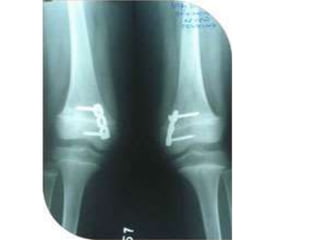

Deformity correction by ilizarov fixator

• Deformity correction indications:

• The following deformities should be considered for treatment, even in

asymptomatic patients:

• 1.distal femoral mechanical valgus greater than 5 degree,

• 2.proximal tibial mechanical varus greater than 5degree, and mechanical

axis deviation greater 15 degree.

• Other asymptomatic deformities should be considered for correction

prophylactically if radiographic

• evidence of degenerative joint disease is seen or if only clinical signs are

detected (eg, positive Trendelenburg sign in a dysplastic hip, lateral thrust in

a varus knee).

• Other deformities that should be considered for treatment include

procurvatum deformity of the distal tibia greater than 15 degree,

recurvarum deformity of the distal tibia greater than 10degree , and varus

or valgus deformity of the distal tibia greater than 10 degree

• Isolated rotational deformities should not be treated unless symptomatic